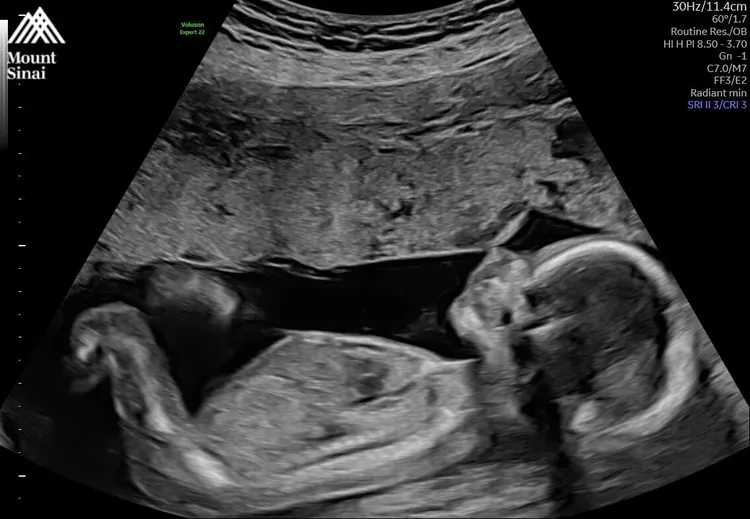

今廣告小妹曬出寶寶的超音波照,透露「等了四年,助理回家了;等了三年,小聰回來了。謝謝大家的掛念,沒發文的日子裡,我一切都好。祝願你們也好。」網友見狀也紛紛留言恭喜,「太棒了,祝福一切平安順利」、「哇,是小班長啊」、「恭喜,孩子是珍寶,眼眶泛淚」。

廣告小妹曬超音波照。翻攝廣告小妹臉書